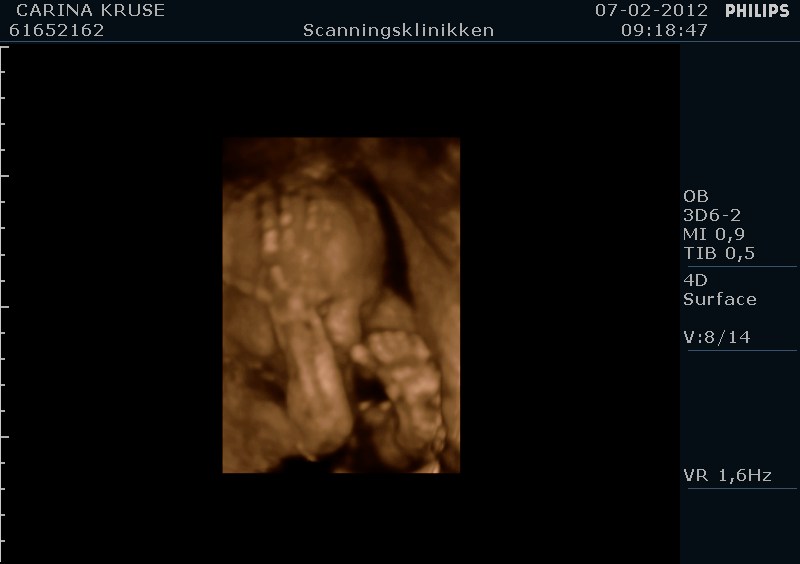

Her er lige et par billeder af vores lille babypige